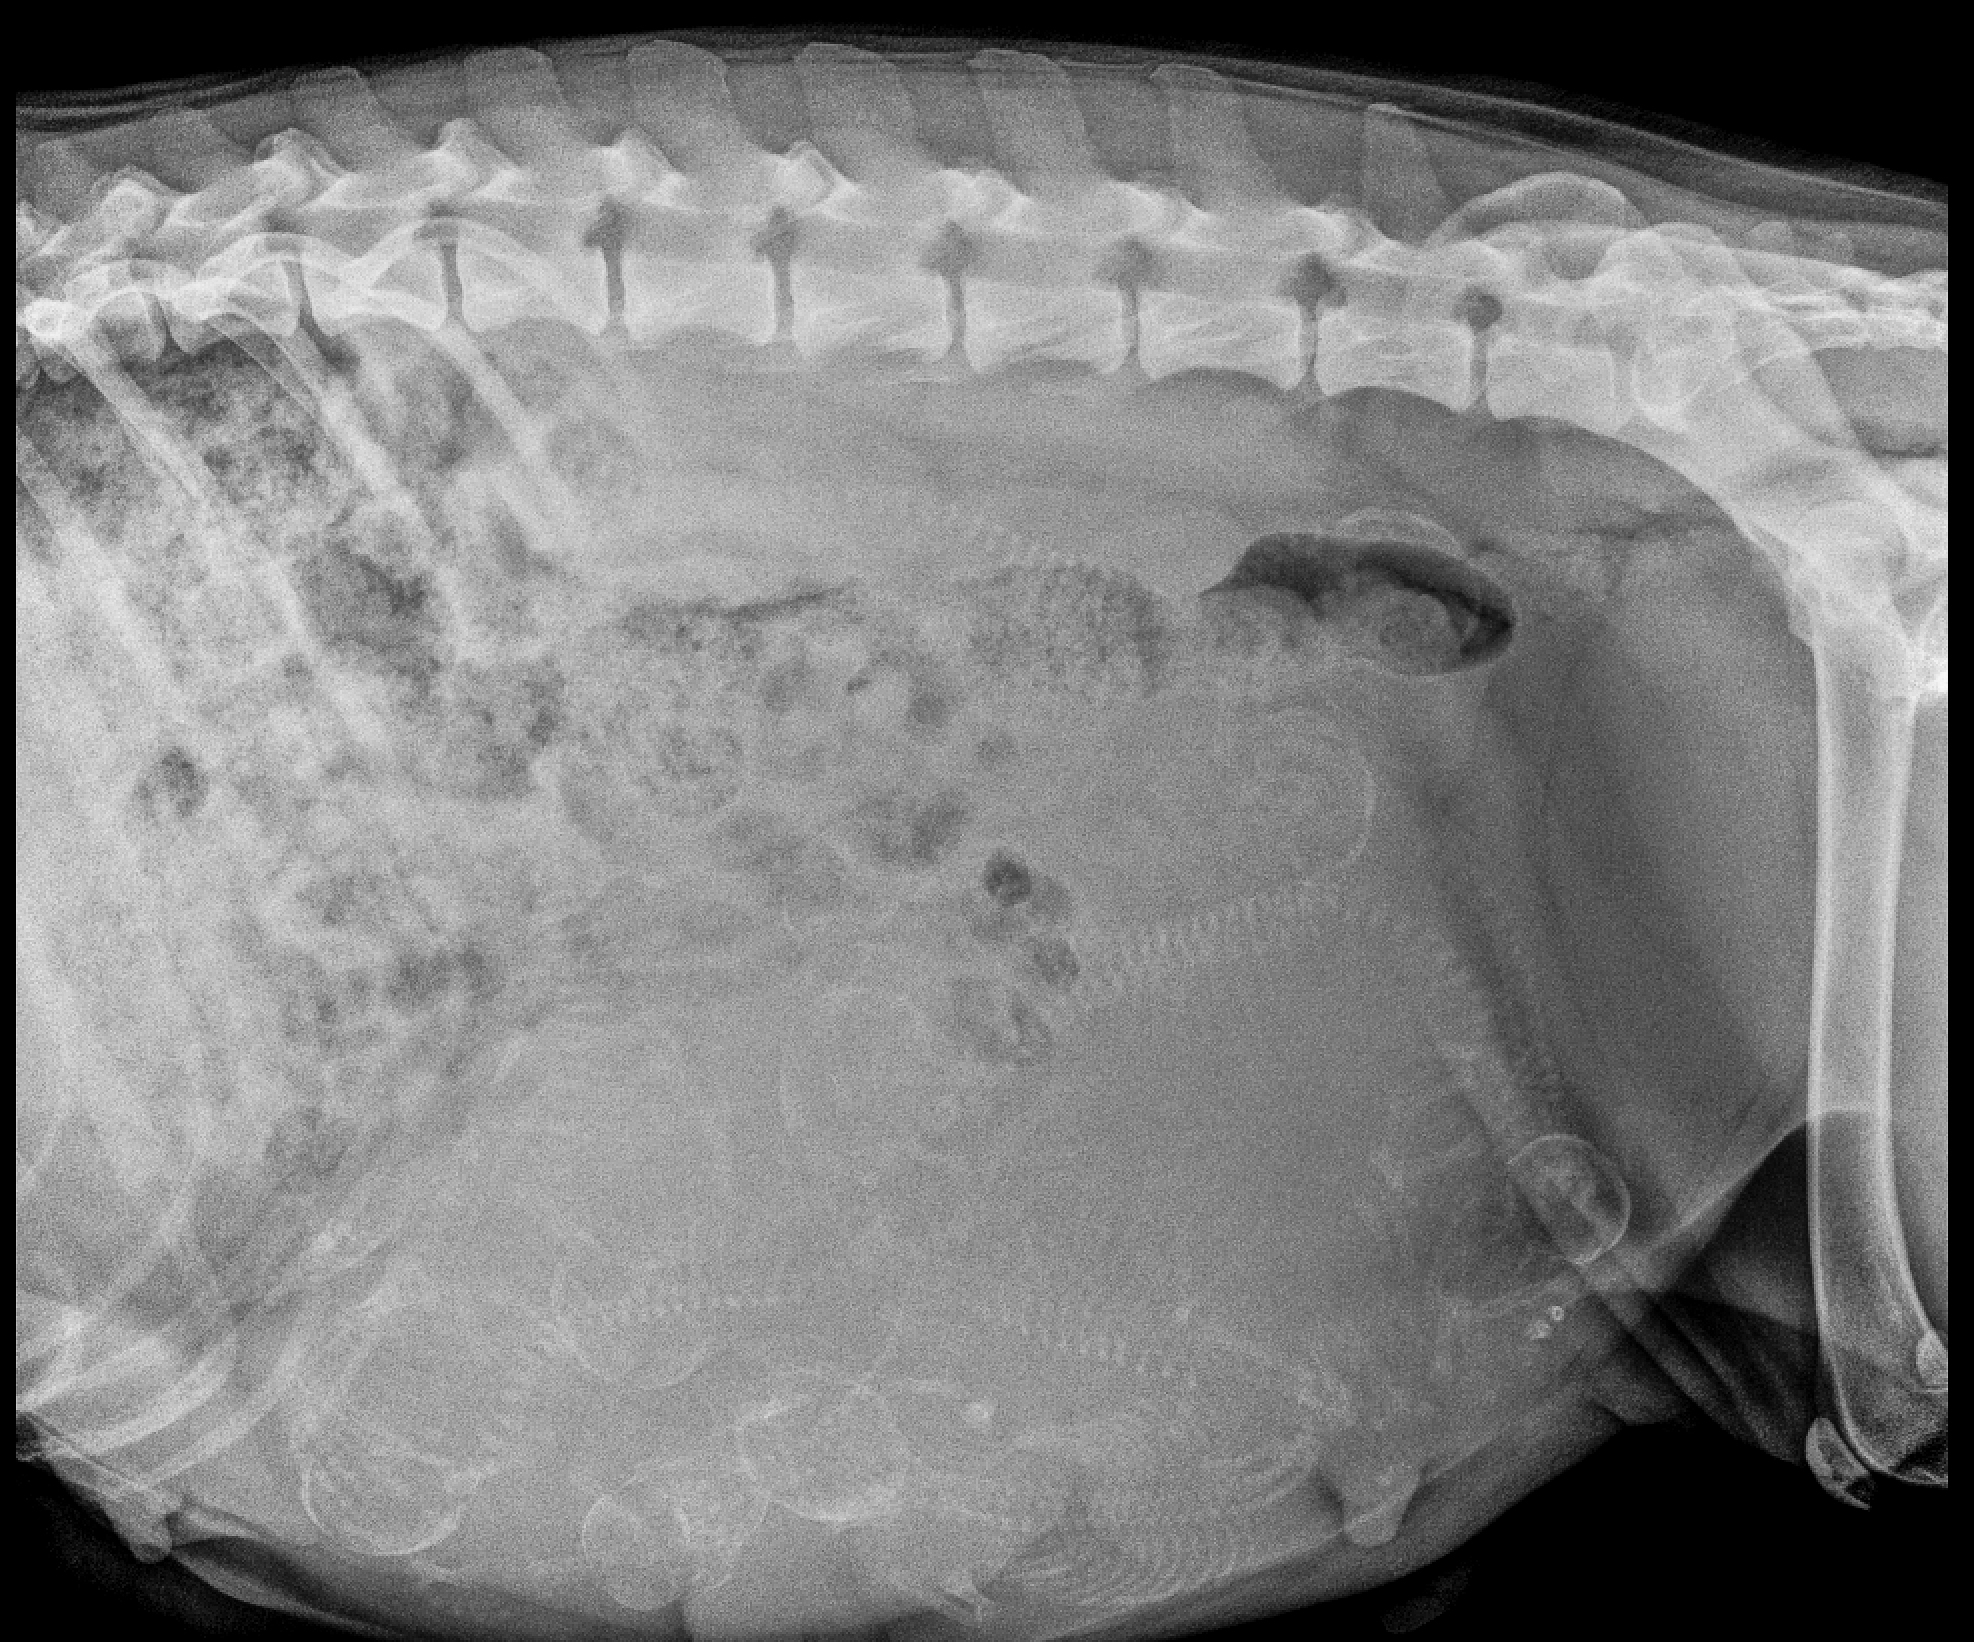

Pregnancy x-rays shows a LOT of puppies!

Well, the big day will be next week! We have opted to do a scheduled C-Section on 7/5/19 for several reasons. First off, Deja has at LEAST nine puppies seen on her pregnancy x-ray! It is possible there may be a 10th puppy hiding… It’s possible! That is a LOT of puppies to whelp!

Can you count puppies? Remember for each skull, you need to trace the corresponding spine!

A “cheat sheet” counting those skulls and spines! That is a LOT of puppies!